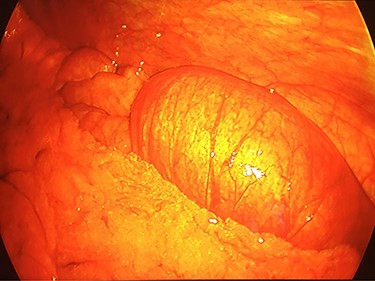

Intra-operative laparoscopic view of the intussuscepted small bowel prior to resection.

On exam, the patient was afebrile and tachycardic to 110 beats/minute. He appeared in acute distress but was oriented to person, place and time. His abdomen was non-distended but was rigid with severe abdominal pain with palpation in all four quadrants. Laboratory evaluation identified a leukocytosis to 16.5 K/mm3 with normal serum electrolytes and liver function tests. A CT was obtained, which showed a 4-cm segment entero-enteric intussusception without obstruction or signs of ischemia with non-specific bowel thickening proximal to the intussusception (Fig. 1). Given peritonitis on exam, the patient was taken to the operating room where the entero-enteric intussusception was identified and resected in bloc (Figs 2 and 3) No masses were palpated in the surgical specimen.

The patient recovered well and was discharged on post-operative day 3. Pathologic review of the resected entero-enteric intestine showed intramural hemorrhage and surface changes consistent with early ischemia. No malignant tissue or other identifiable cause of the intussusception was observed. He has since been seen in clinic with near resolution of his chronic abdominal pain.